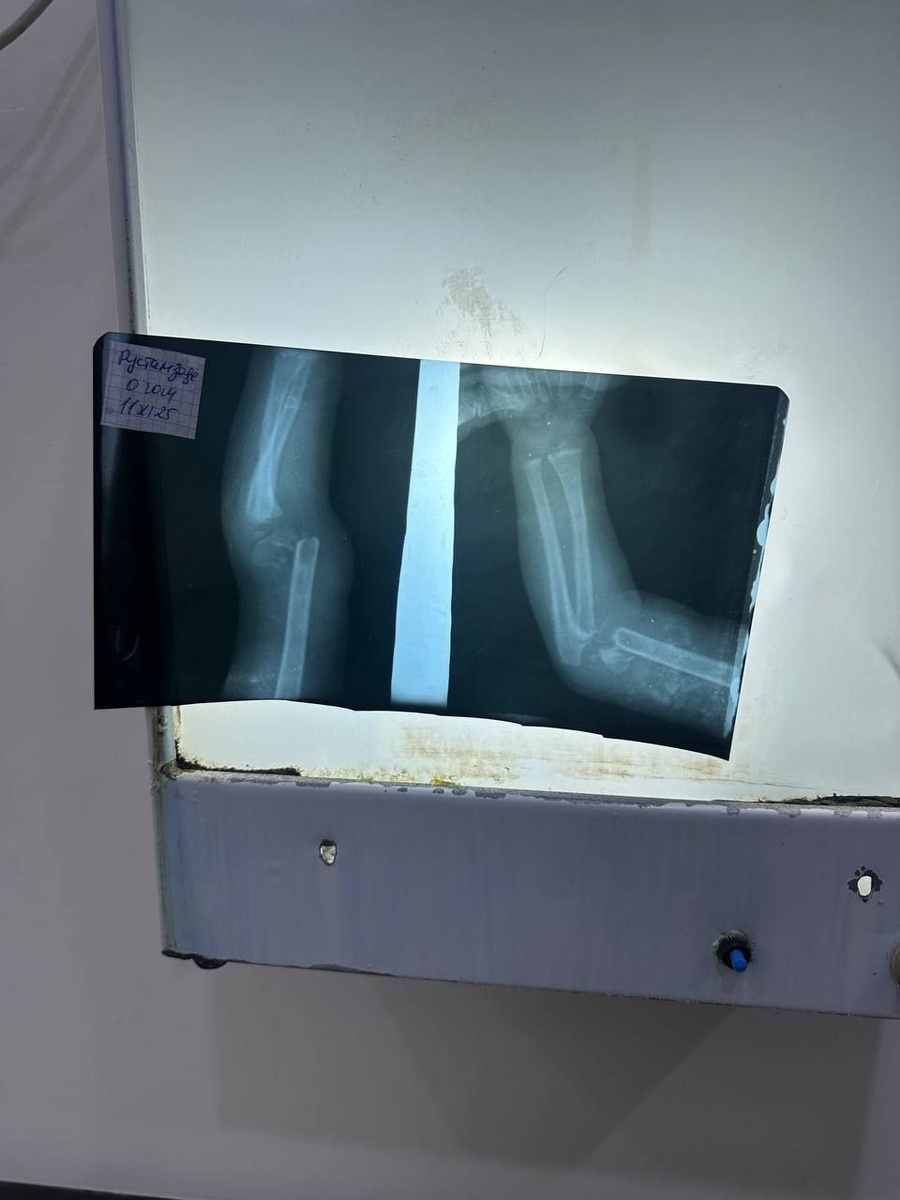

1.5 года девчушке. Из-за того, что слишком активная - развалила ручку.

Закрытое вправление, гипс.

3 недели прошло, градус так себе.

По рентгену оставшееся смещение беспокоит.